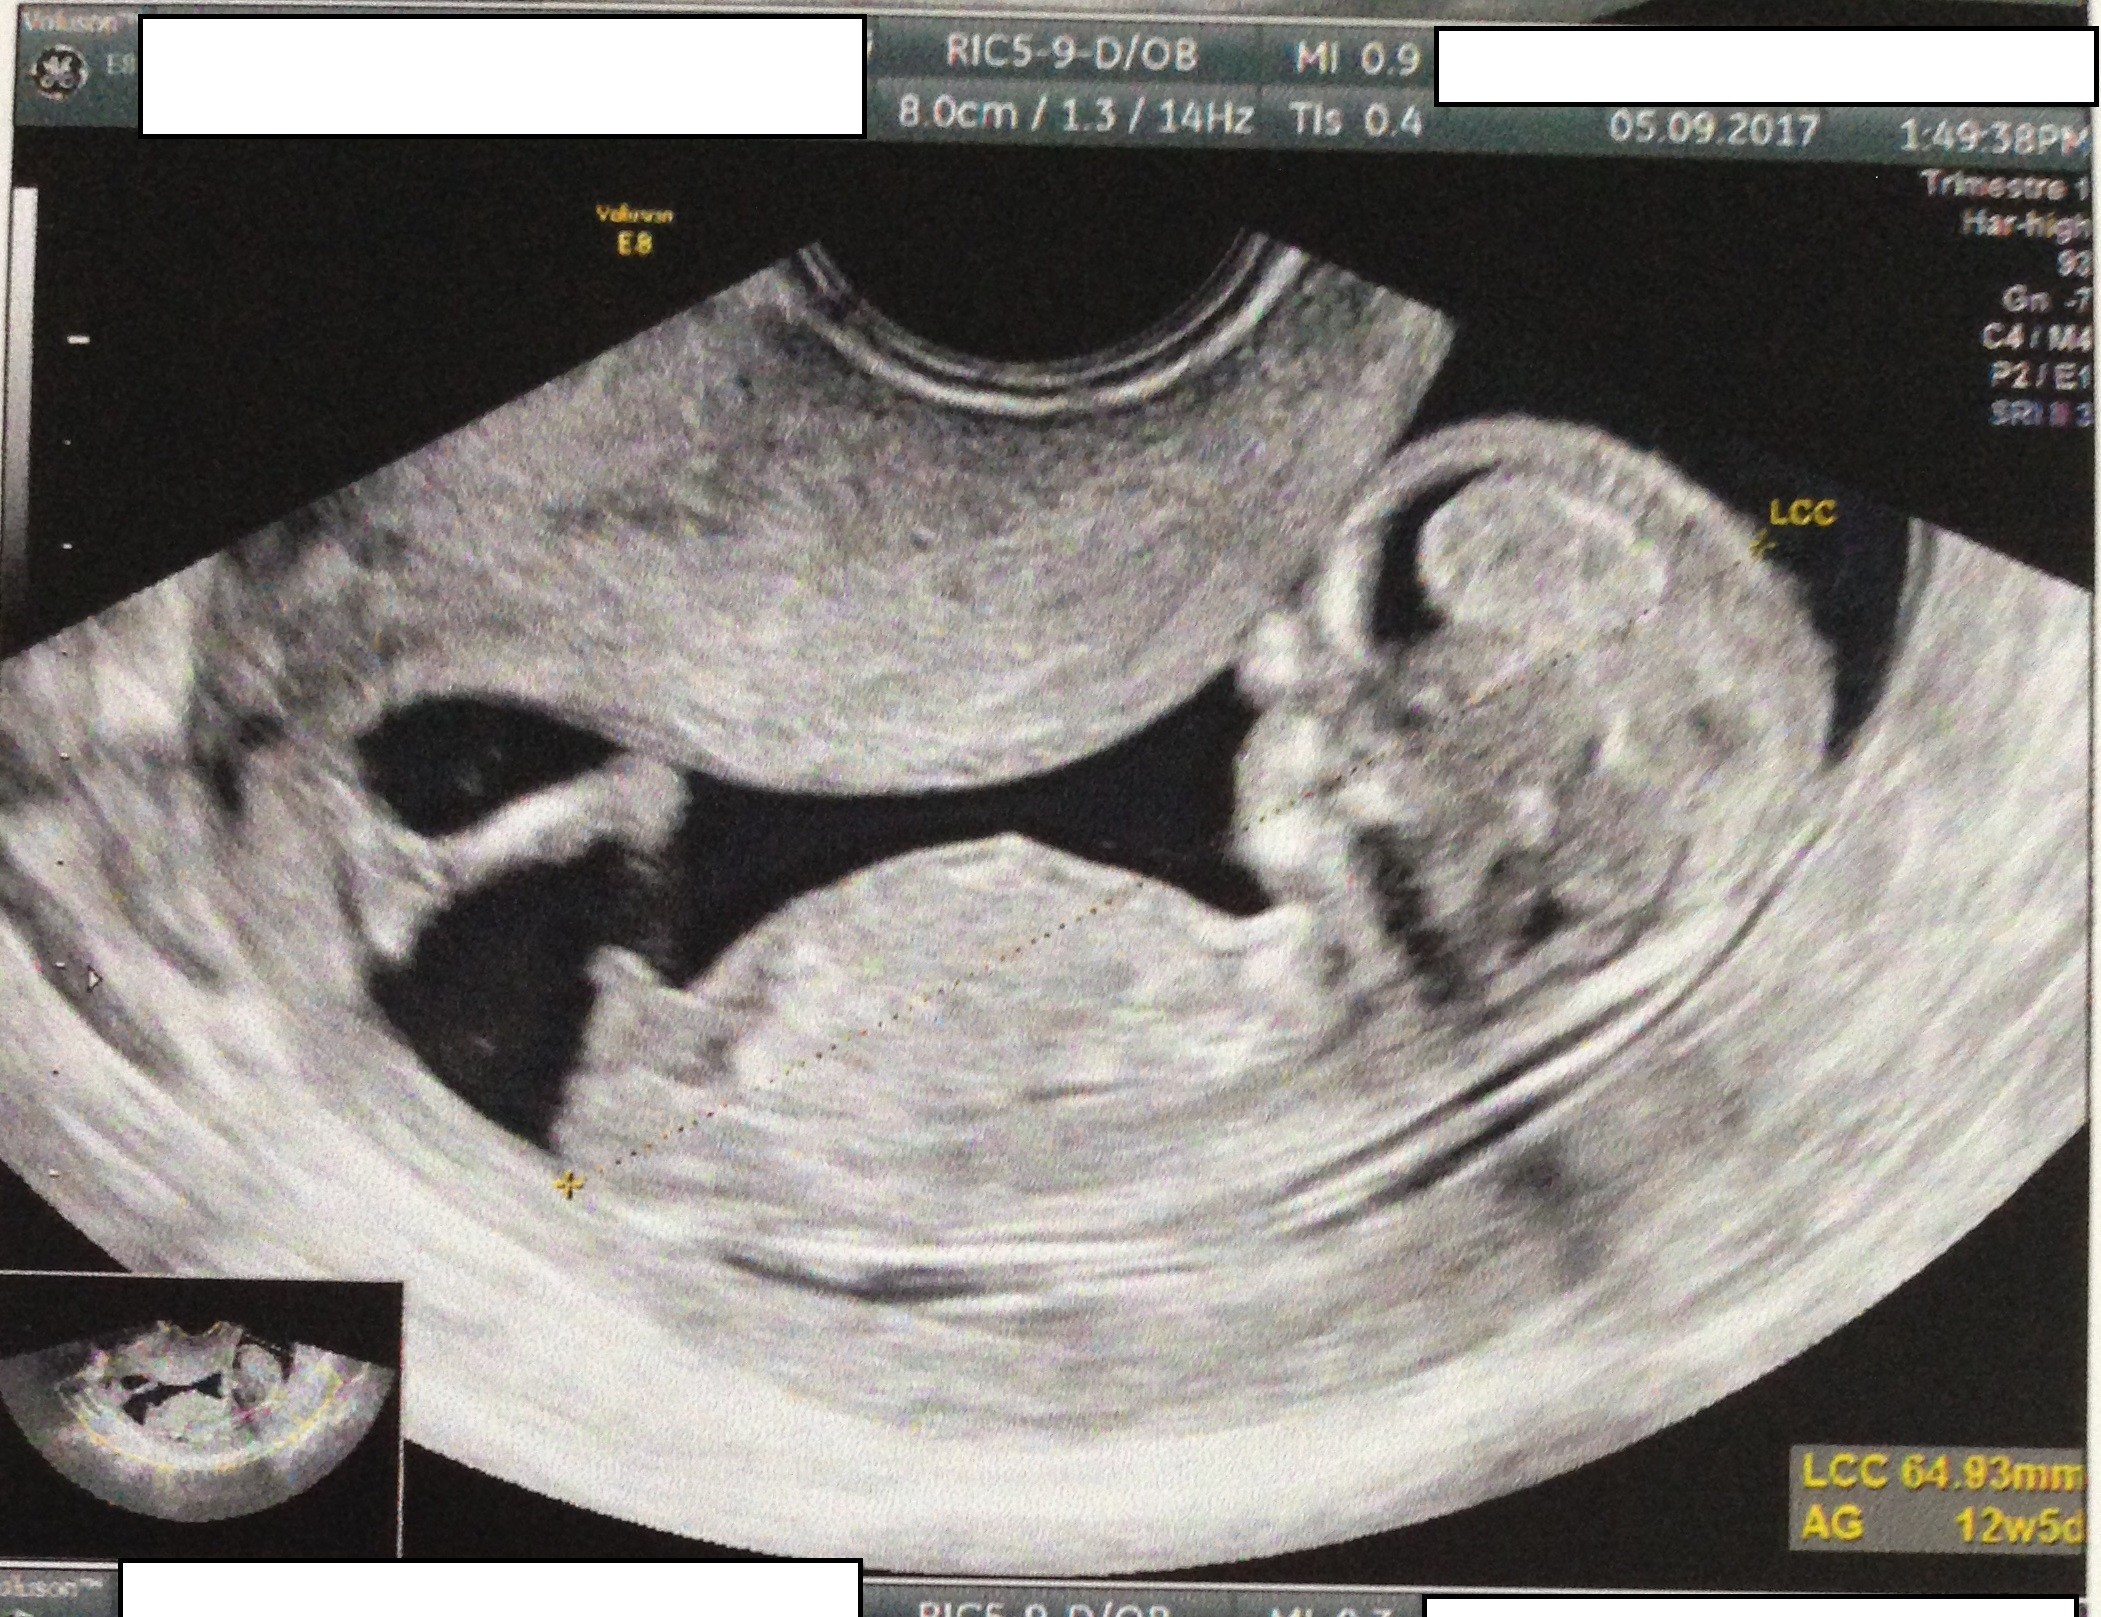

M Maman de bébé E ☀️ 14 août 18 Coucou les filles rdv T1 hier pour moi à 12sa4 et l'échographiste qui ns dit toutes les mesures sont parfaites! Echographie à 8 SA Les achats Petits craquages La liste de naissance de Bébé 4 Ce lundi 8 janvier avait lieu une étape importante, ma seconde écho, celle des 12 SA où avec le papa nous avons pu (re)voir notre toutpetit Il mesure 55 mm, sa clarté nucale est normale Il bouge bien, son petit coeur bat comme il fautIl pèse approximativement entre 50 g et 65 g Très actif et très sportif, le bout'chou tel un athlète ne cesse de remuer, de sauter et de gesticuler dans votre utérus A la fin

Echo 12 SA 3 jours le 27/07 bébé mesure 63cm et son coeur bat à 153p/m 80% de chances que tu sois une petite princesse On t'aime !30 août 12 To be or not to be PMA Catégories Grossesse Étiquettes Echographie 12 saLa clarté nucale voilà un élément morphologique dont on ignore généralement totalement l'existence tant qu'on a pas été enceinteQu'estce donc ?

A voir également Sexe bébé 12 SA Gouter bebe 12 mois Guide Taille bebe 12 sa Guide Miel bebe 12 mois Guide Journée type bébé 12 mois Guide Bebe 12 kg quel age Guide Votre réponseRendezvous avec nos 2 petits bébés d'amour11ème semaine de grossèsseOn la mesure lors du premier trimestre (jusqu'à 14 SA) Elle est de 55 mm en moyenne à 12 SA PC Périmètre Céphalique ou Crânien Il s'agit du tour de tête de votre bébé A la première échographie (12 SA) 68 mm en moyenne A la seconde échographie (22 SA) 199 mm en moyenne A la troisième échographie (32 SA) 297 mm en moyenne

Dernier message posté le à 10h54 Mélodie Nierengarten à 10h43 Alerter Copier le lien Le lien a été copié dans votre pressepapier Bonjour, Voici mon post parmi tant d'autres pour essayer de deviner le sexe de mon bébéLe soir de la première échographie OFFICIELLE celle des 12 semaines d'aménorrhée Nous sommes allés dans un cabinet d'échographie recommandé par madame gynécoSelon les mesures nous étions hier entre 12 sa 3 pour la longueur fémorale (qui est de 803 mm) à 12 sa 6 pour le périmètre crânien (qui est de 229 8mm), et avec 165 bpm pour la fréquence cardiaque !